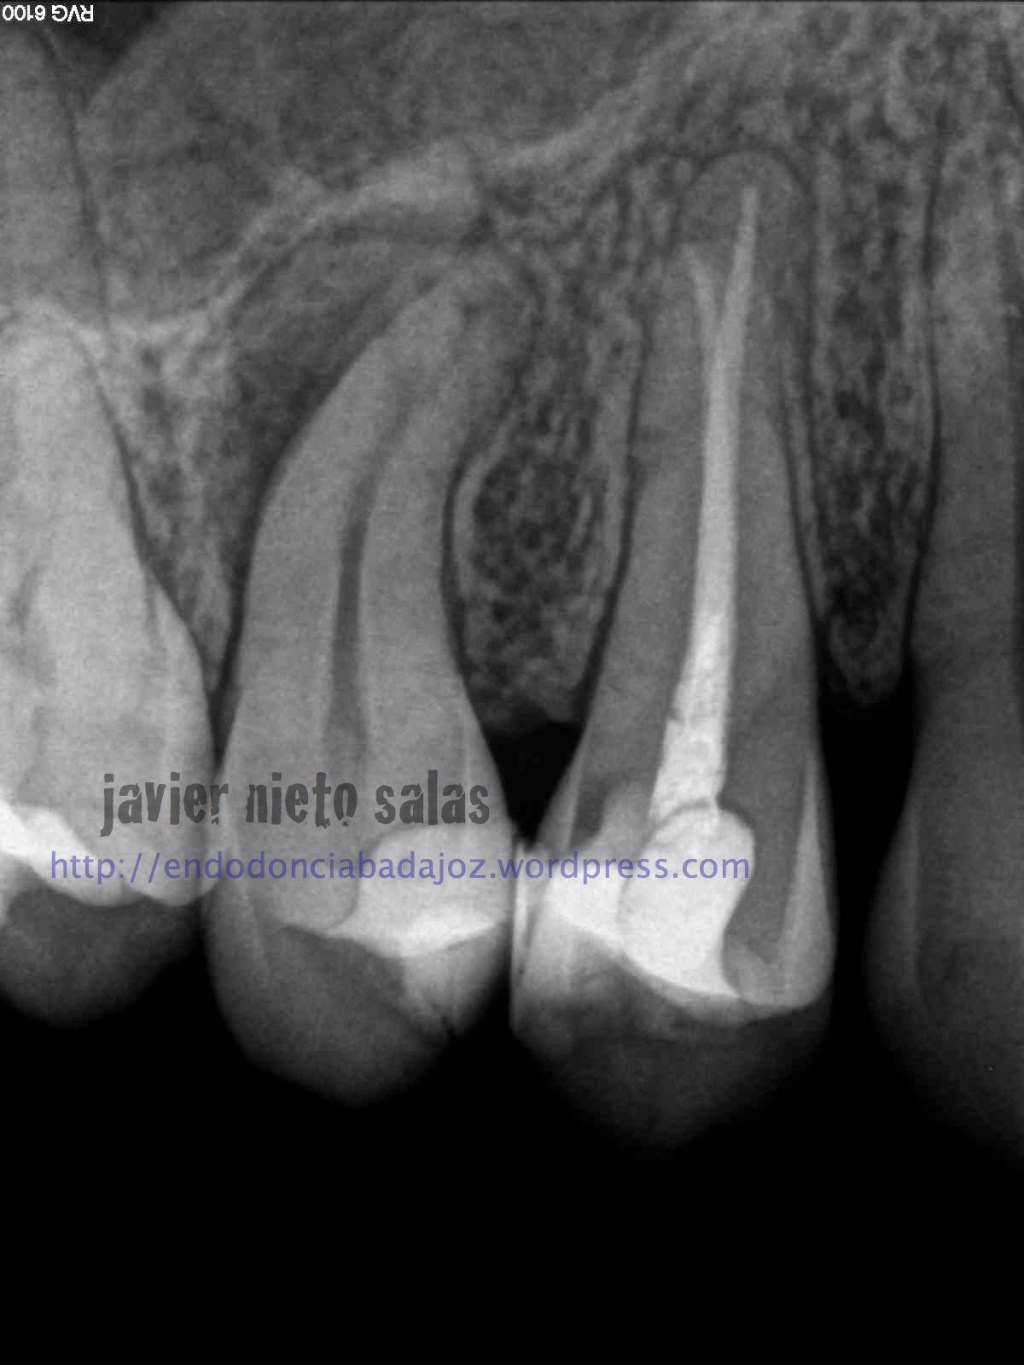

En el  primer caso de hoy, podemos ver la importancia de pararse a ver la radiografía inicial, el tamaño de la lesión y el posible origen, algo, a mi parecer, bastante importante.

Así pues, en esta primera imagen vemos la lesión lateral que nos hace sospechar de una posible salida a ese nivel. Modificando nuestra técnica de limpieza y obturación:

Después de unos 9 meses, la paciente nos llegó a revisión, la lesión ha regenerado correctamente, éxito en el tratamiento: